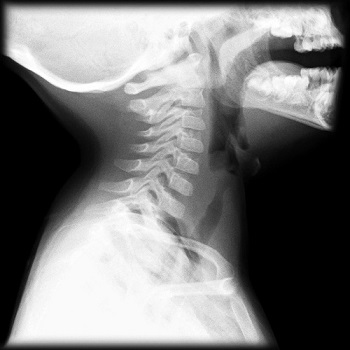

- Gold Standard: Radiography of the airway

If positive for croup, radiograph will characteristically show Steeple sign, so named because the subglottic narrowing looks like a steeple. Lateral view may show overdistention of the hypopharynx on inspiration.